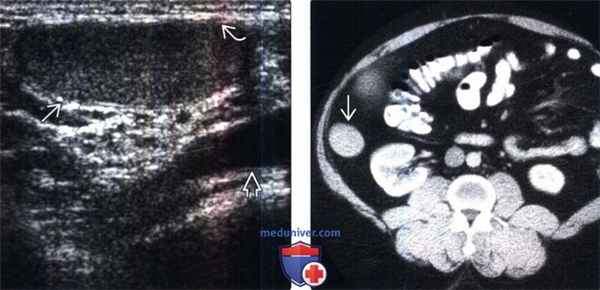

2. УЗИ при крипторхизме:

• Овоидное гомогенное образование с четкими контурами:

о От изо- до гипоэхогенного сигнала по сравнению с нормальными яичками

о Меньше чем нормальные опустившиеся яички

• Эхогенная линия, представляющая из себя перегородку яичек, помогает в дифференцировке их от окружающих мягкотканных образований

• Лучший метод обнаружения яичек в предмошоночной области прямо за наружным паховым кольцом или в паховом канале

3. КТ при крипторхизме:

• Гиподенсивное образование выше мошонки по пути опущения яичек

(Слева) УЗИ пахового канала в косой плоскости: глубоко в подкожной ткани определяется овоидное гипоэхогенное яичко В и фасция. Обратите внимание на бедренные сосуды. Паховый канал является самым частым местом расположения неопущен-ных яичек и может проявляться в виде пальпируемого образования в паху.

(Справа) КТ с контрастированием, аксиальный срез: овоидное мягкотканное образование В в забрюшинном пространстве, сбоку от почки. Это образование может быть принято за другие мягкотканные образования или лимфоаденопатию, поэтому очень важно учитывать анамнез. На более низких срезах отсутствует семенной канатик.